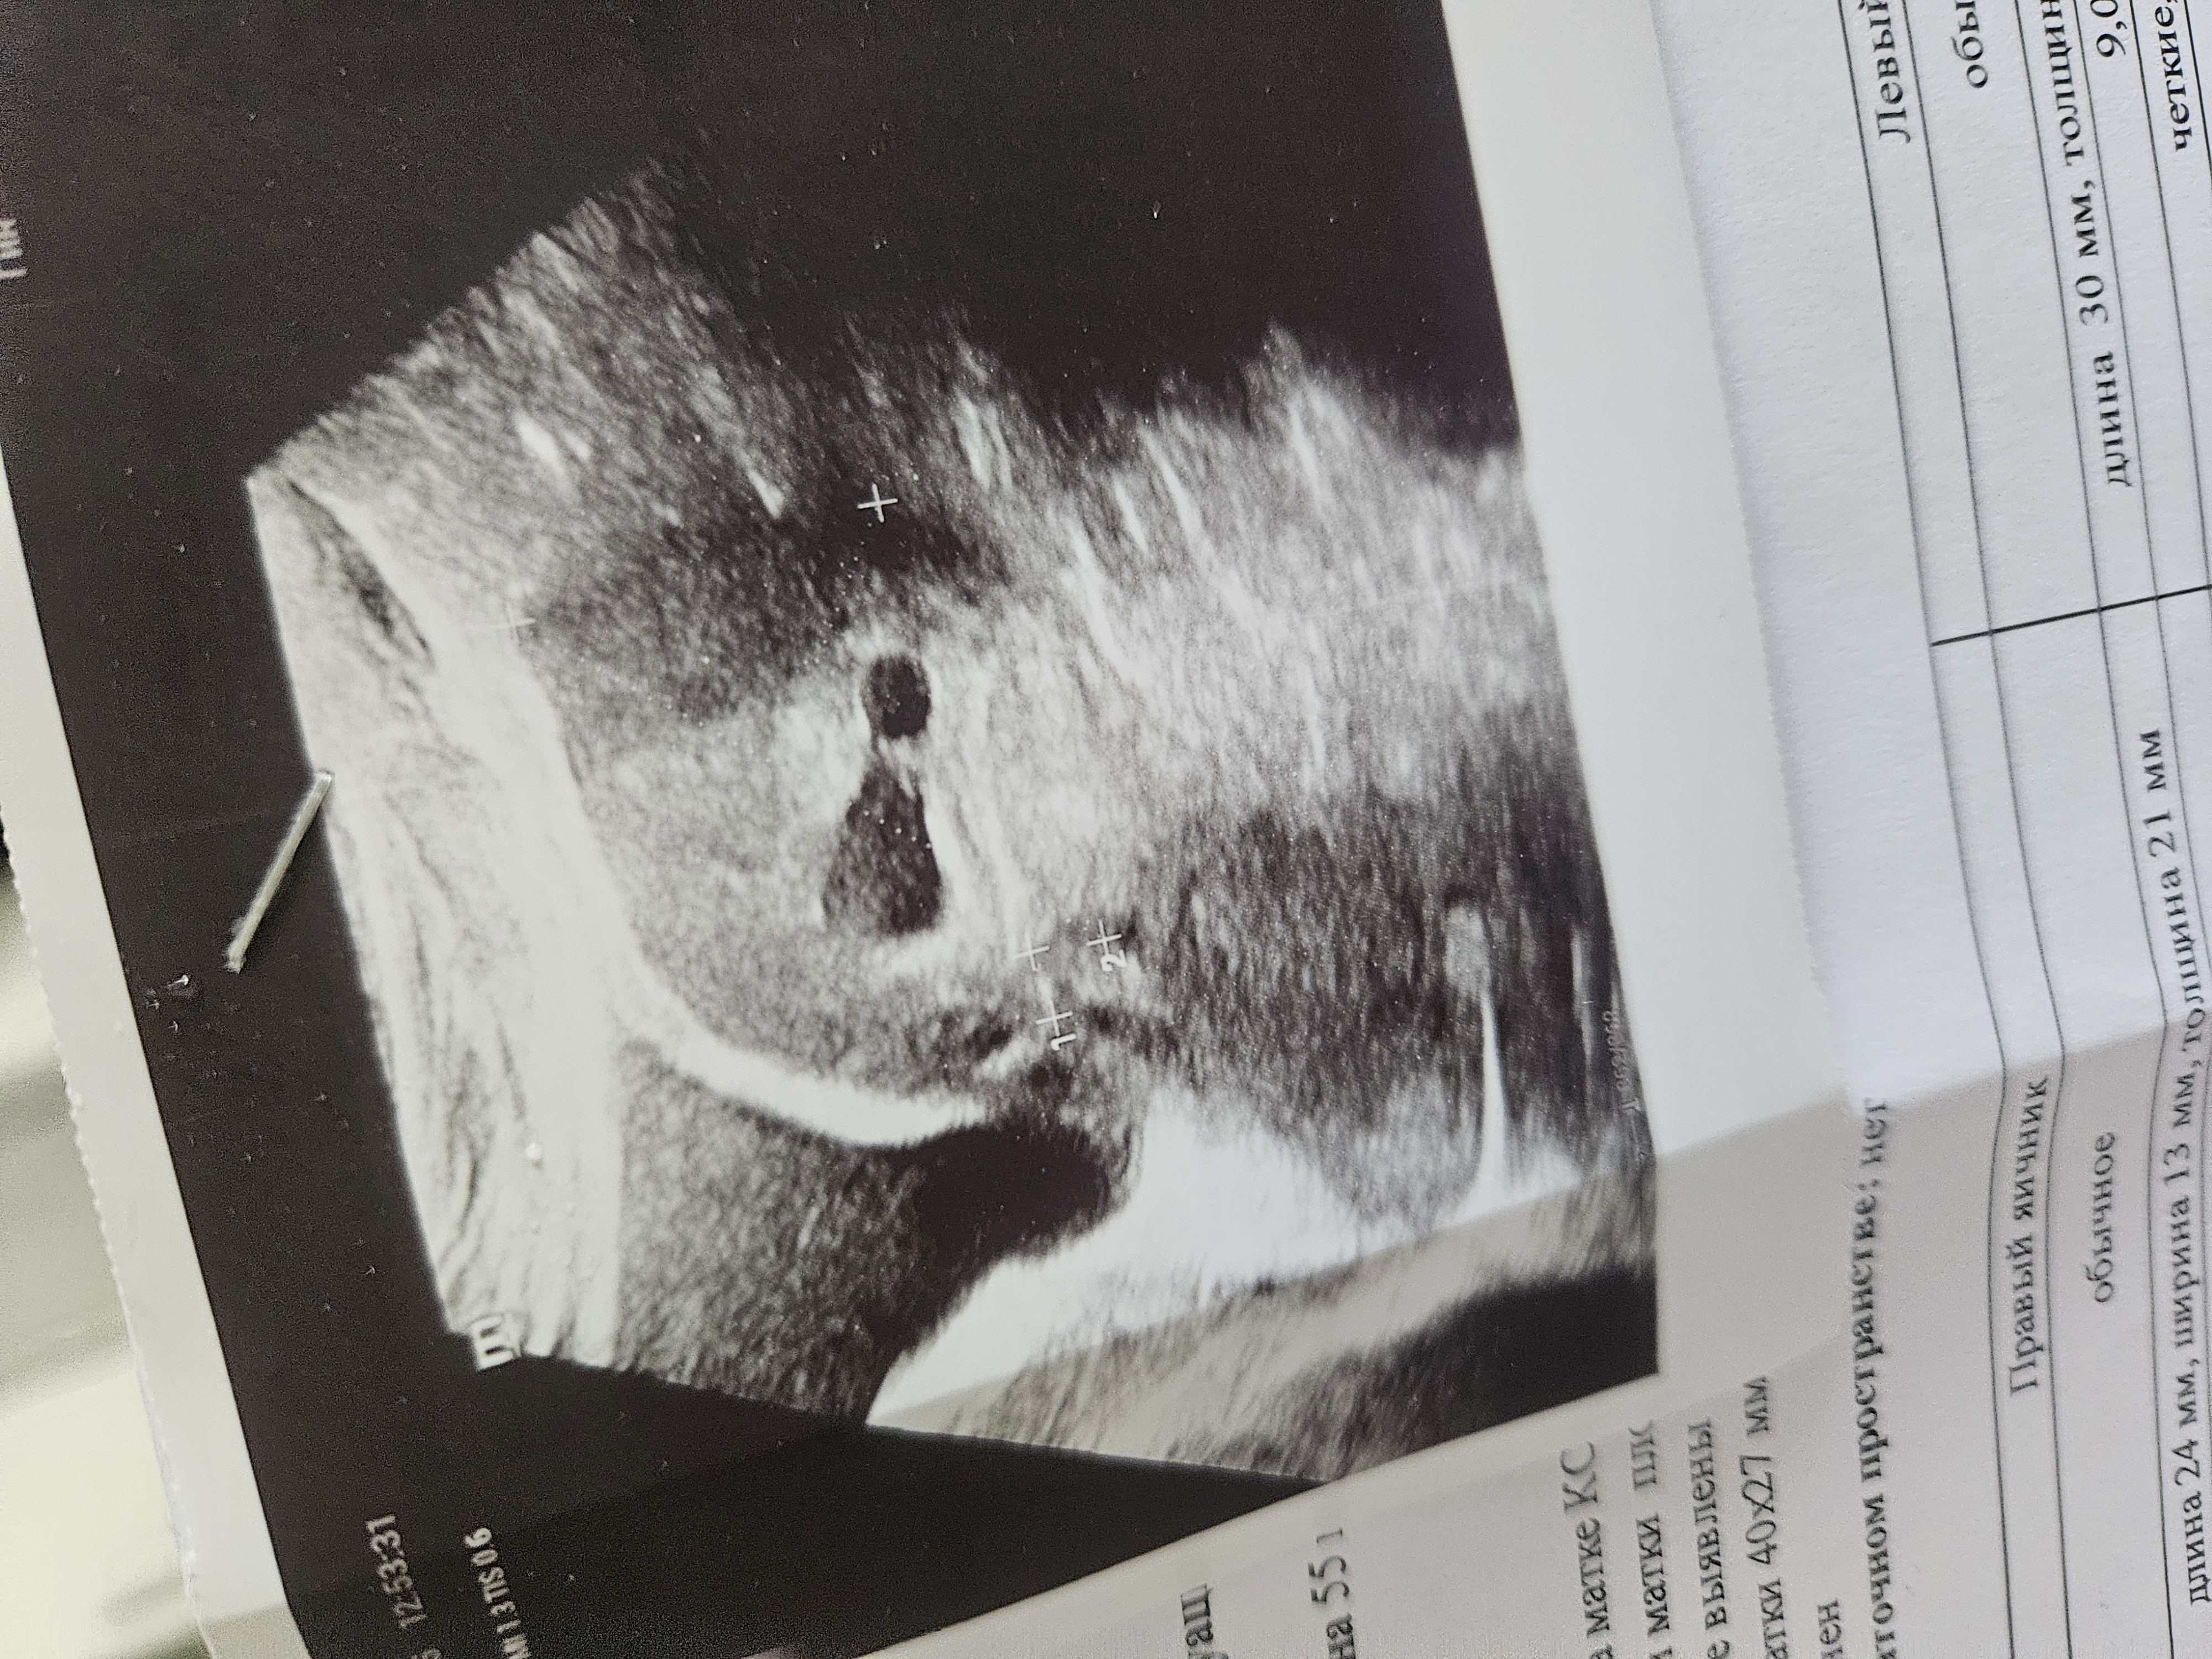

Вторая беременность, срок 35-36 недель.

Рубец намерили на последнем узи 1,5 мм.

Врач сказала это очень мало, напугала.

Сказала в 36 недель ровно ложиться в роддом. Кто был в такой или похожей ситуации? Как все прошло? До какого срока доходилИ?